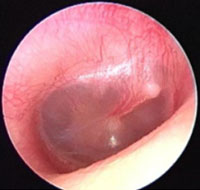

Normal Tympanic Membrane

TM is translucent

Handle of the malleus is vertical

No erythema